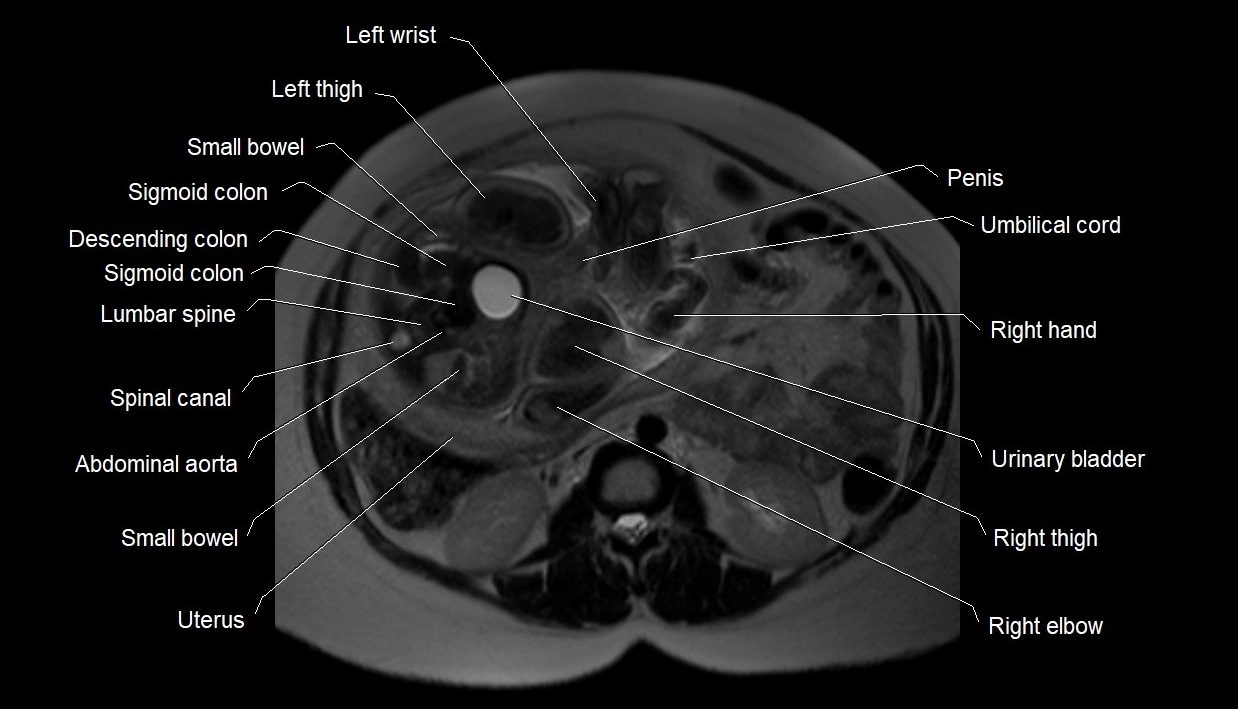

MRI Appearance

T2 HASTE (T2 GRE):

• Amniotic fluid shows very bright hyperintense signal

• Provides natural contrast against fetus and placenta

• Small particles (vernix) may appear as scattered hypointense foci within bright fluid